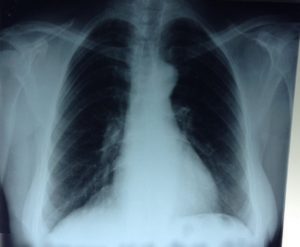

- Лучевая диагностика. Рентгенография и КТ грудной клетки являются наиболее информативными методами исследования диафрагмы. На рентгенограмме визуализируется высокое расположение одного из куполов (уровень II–V ребра). При рентгеноскопии обнаруживается парадоксальное движение диафрагмального свода. Использование контраста позволяет выявить перегибы пищевода, желудка, смещение органов пищеварения кверху. КТ наиболее точно определяет степень релаксации, помогает распознать вторичную патологию внутренних органов.

Основным методом диагностики релаксации диафрагмы, как и диафрагмальных грыж, является рентгенологическое обследование больного.

Из органов брюшной полости высоко кверху вдаются желудок и толстый кишечник, затем селезенка, реже тонкий кишечник. Смещенный кверху желудок претерпевает те же изменения положения, что при диафрагмальной грыже: большая кривизна обращена кверху, прилегает к диафрагме. Легкое сдавлено соответственно высоте подъема диафрагмальной перегородки, сердце при левосторонней релаксации смещено вправо.

Наблюдаются изменения положения брюшных органов, особенно желудка, толстой кишки, а также сдавление легкого, смещение сердца, весьма схожие с тем, что наблюдается при диафрагмальной грыже.